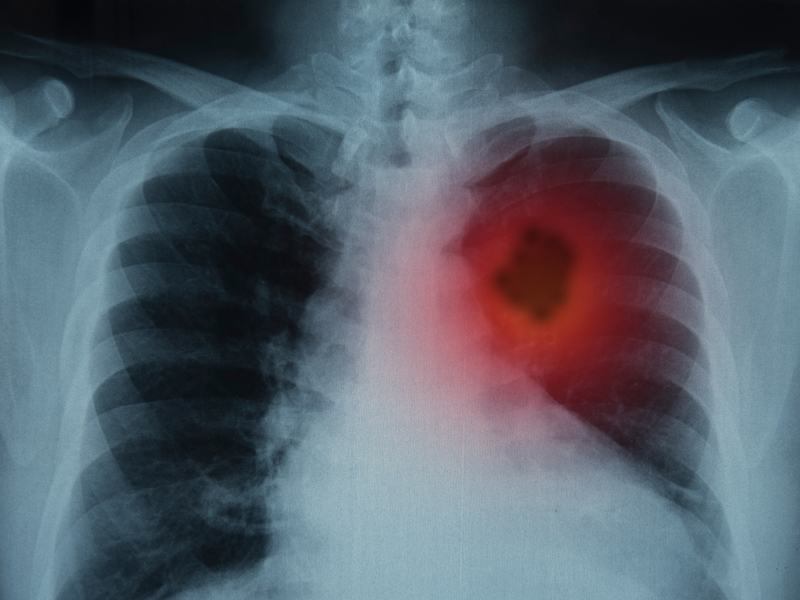

一開始並未在意,後來病情持續加重,才到醫院拍片子,結果發現腰椎部位的骨骼竟然是鏤空的!

進一步檢查發現,這並不是骨質疏鬆導致,而是晚期腎癌 ...

打噴嚏很少會引起腰部疼痛,覃先生打噴嚏腰痛,是腹壓增高,使骨轉移的椎體壓癟從而引起劇烈疼痛,臨床稱為病理性骨折。

正常人的身體骨質非常密實,有彈性,可以起到脊柱支撐作用。而癌症患者則會因骨轉移產生劇烈疼痛,集中在腰椎。轉移癌會使骨骼密度程度下降,將原本緻密骨骼破壞成鏤空狀,醫學上稱為溶骨性破壞。